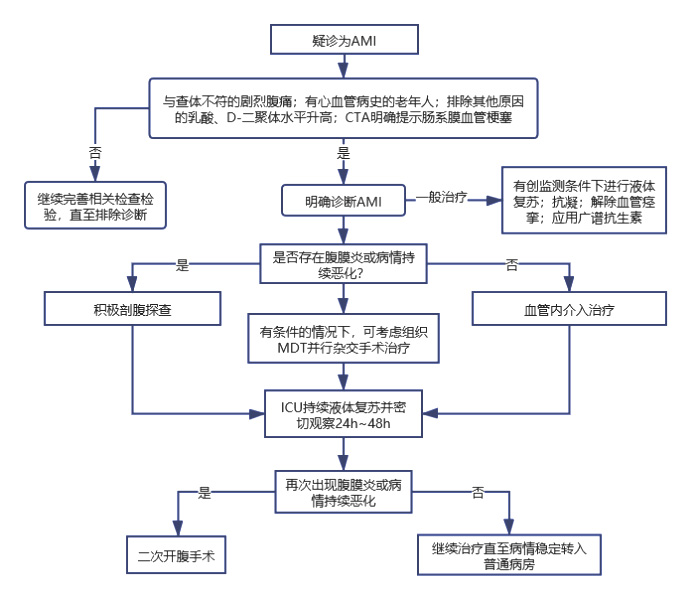

6.2 影像学检查(插入AMI的典型CTA影像,图 2)

| 图 2 CTA下肠系膜血管病变 |

目前,CTA成像技术已正式取代了血管造影作为影像学首选检查(图 2)。

AMI病情进展的情况下,CTA可提示肠道不可逆的缺血(肠道扩张和肠壁增厚,内脏增强影像的减弱甚至消失,肠壁及门静脉积气等)和腹腔内存在的游离气体[2]。对于NOMI的患者而言,CTA可能提示肠道缺血并在肠系膜血管周围显示出游离气体。而在VAMI患者中,静脉相CTA甚至可直接提示肠系膜上静脉血栓[21]。此外,VAMI的相关表现还包括肠壁增厚,积气,脾大和腹水等。

故高度疑诊情况下,治疗团队应充分评估患者的病情,若条件允许,即使患者存在一定程度的肾功能不全,仍建议尽早行CTA检查。因为延诊、误诊或管理不善所带来的后果,相对肾脏暴露于碘化造影剂而言更为有害[7]。

7.3 多学科综合救治(Multi-disciplinary Team, MDT)与杂交手术近年来,由于介入技术的发展与治疗效果上显现出的优越性,越来越多的研究者倾向于使用介入治疗作为AMI的一线救治手段。但由于AMI的患者往往病情危重且进展迅速,进行介入手术前常无法准确判断是否存在肠道坏死。另一方面,即使术中取得了技术上的成功,但由于术后肠系膜血管持续痉挛或血管内再栓塞的发生,对于部分患者而言,在初次手术后(通常是24 h内或更短的时间),其病情将再度恶化。此时常需二次手术,进行剖腹探查以切除坏死组织。故外科医师应随时待命。且患者在介入术后建议立即入住ICU,在持续液体复苏的同时进行密切观察(见图 3)。

| 图 3 AMI简易诊治流程图 |